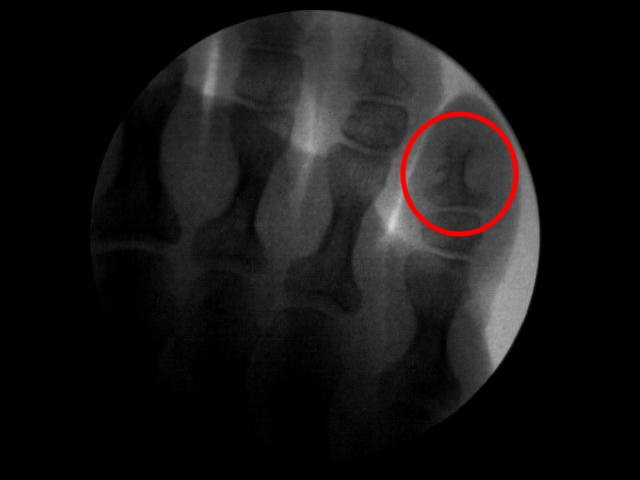

Los molestos y dolorosos «ojos de gallo» que suelen aparecer en los pies entre los dedos y/o encima de los mismos tiene solución definitiva y consiste en realizar una microcirugía local para el pulido del hueso que está generando dicha patología en la piel. Lo que ocurre generalmente es que la forma picuda que tienen las falanges (huesos de los dedos), generan junto con la rotación de algún dedo implicado y el calzado estrecho una presión constante en la zona y ello da lugar a un endurecimiento de la piel que finalmente se convierte en un callo circular siendo muy doloroso en ciertas zonas debido a la opresión que soporta.

La intervención es muy corta y sencilla, bajo anestesia local de la zona a intervenir y mediante cortes milimétricos podemos acceder a la zona picuda del hueso implicado y pulirlo eliminando así el pico óseo que genera presión sobre la piel afectada. Al tratarse de microcirugía no requiere de puntos de sutura en piel, el sangrado es mínimo y la recuperación inmediata.